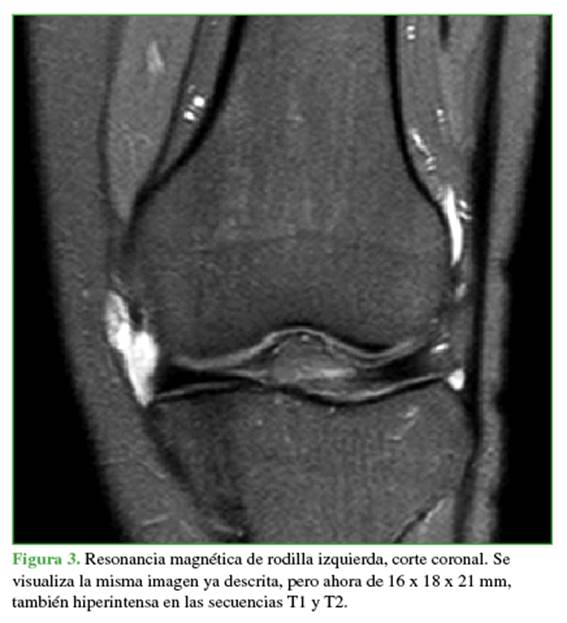

En ese momento, se solicitó el par radiográfico correspondiente, una ecografía Doppler y una RM. La radiografía no mostró particularidades. En la ecografía, la lesión fue informada como un “proceso nodular mixto sólido quístico con calcificación proximal, de aproximadamente 22 x 5 mm, impresionando estar en la relación con la articulación femororotuliana, sugestivo de origen sinovial” (Figura 2). En la RM, se visualizó la misma imagen ya descrita, pero ahora de 16 x 18 x 21 mm, también hiperintensa en las secuencias T1 y T2 (Figura 3).